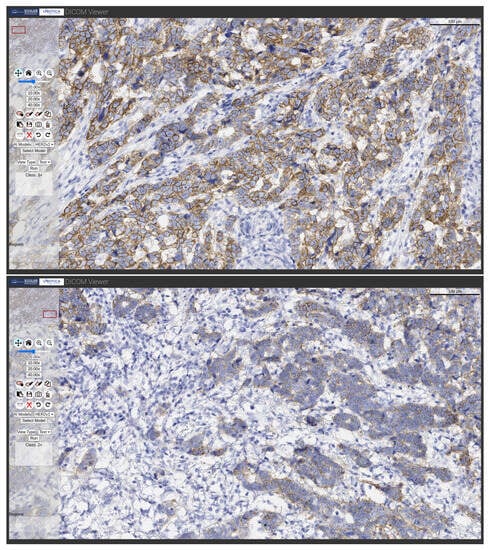

• Text: It displays the outcome in the result text box. The processing is limited to the zoomed-in region selected by the user, performing a single inference and classifying it as appropriate. This view is available for the HER2 model. Some examples are illustrated in Figure 6.

Figure 6. Examples of HER2 model processing showing different outcomes with text type outputs.